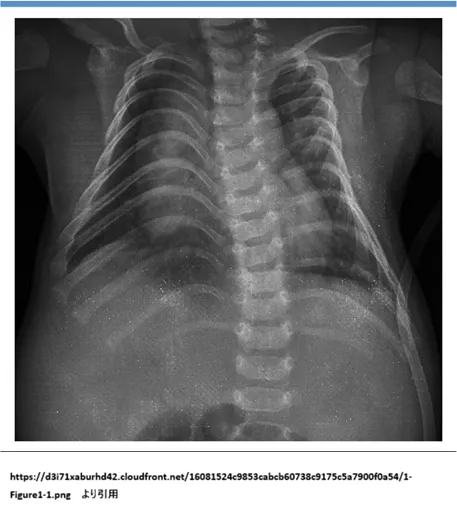

💡 用語解説:「コートハンガー肋骨」とは?

「コートハンガー肋骨(coat-hanger ribs)」は、胸部X線で肋骨が上向きに強く湾曲し、肩掛け(ハンガー)の形に見える所見です。鏡-緒方症候群(Kagami-Ogata syndrome:KOS)でよくみられ、KOSを疑う重要な手がかりになります。

ただし、画像所見だけで確定診断はできません。KOSは刷り込み(インプリンティング)異常が本態のため、第一選択はメチル化解析で刷り込み異常を確認し、その後に必要に応じてCMAなどで原因(欠失やUPD)を精査します。

| コートハンガー肋骨 | 肋骨が上向きに湾曲し、肩掛け(coat-hanger)のように見える | KOSを強く疑う重要所見 |